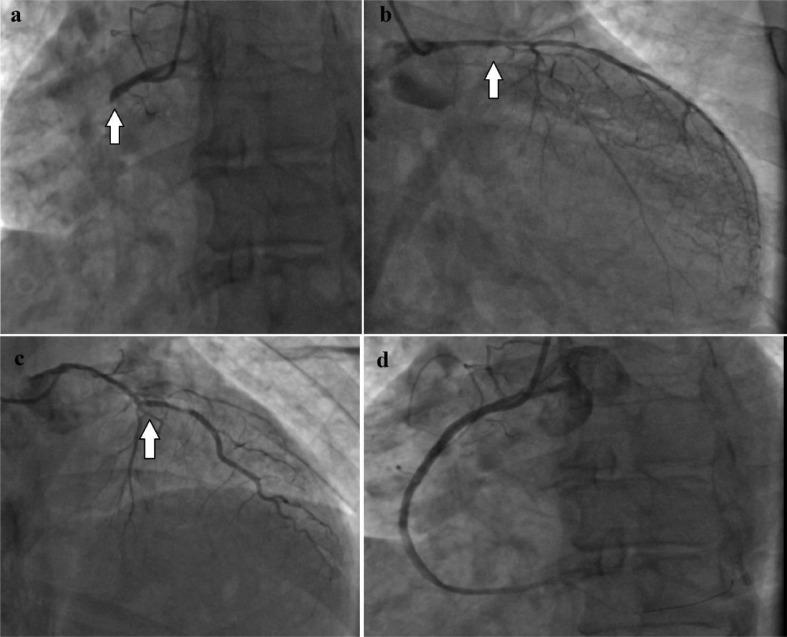

Simultaneous occlusion of more than one coronary artery is uncommon and associated with poor prognosis. We reported a particular case of a 62-year-old patient, who presented with an inferior ST-segment elevation myocardial infarction with right ventricular involvement complicated by cardiogenic shock, sinus bradycardia, and an extensive echocardiographic ischemia with severe left ventricular systolic dysfunction. Coronary angiography revealed occlusion of 3 major coronary arteries. Primary percutaneous coronary intervention of the right coronary artery was performed with hemodynamic recovery, chest pain, and ST-segment resolution. Treatment for heart failure with reduced ejection fraction was initiated, with a good outcome.

同时闭塞多条冠状动脉并不常见,且预后较差。我们报告了一例特殊病例,一名62岁患者,表现为下壁ST段抬高型心肌梗死伴右心室受累,并并发心源性休克、窦性心动过缓,以及广泛的超声心动图显示的心肌缺血伴严重左心室收缩功能障碍。冠状动脉造影显示3条主要冠状动脉闭塞。对右冠状动脉进行了直接经皮冠状动脉介入治疗,血流动力学恢复,胸痛缓解,ST段回落。开始了射血分数降低的心力衰竭治疗,效果良好。